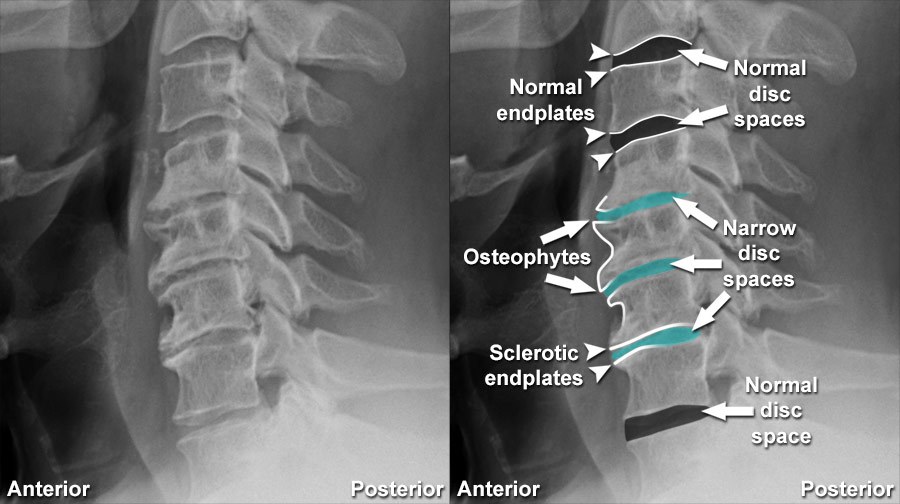

Diagnosing compressive myelopathy involves a combination of clinical evaluation and imaging studies. A thorough neurological examination can identify deficits and help localize the level of compression. Imaging studies, particularly magnetic resonance imaging (MRI), are crucial in visualizing the spinal cord, identifying the source of compression, and assessing its severity. Computed tomography (CT) scans and X-rays may also be used to evaluate bony structures and traumatic injuries.

The term "degenerative spine" refers to the natural wear and tear of the spine's structures—such as discs, joints, and bones—over time. This process is often associated with aging but can also result from injuries, genetic predisposition, or lifestyle factors. The degeneration can lead to conditions like herniated discs, osteoarthritis, and spinal stenosis, causing pain, reduced mobility, and nerve-related symptoms.

Degenerative spine conditions arise primarily from the natural aging process, during which spinal discs lose hydration and elasticity, leading to wear and tear. Factors like genetics, obesity, smoking, and poor posture can accelerate degeneration. Repetitive stress from physical labor, injuries, or trauma also contributes to spinal damage. Additionally, conditions like osteoarthritis and herniated discs can exacerbate the deterioration of the spine's structure over time.

Compressive myelopathy can be caused by a range of factors, including degenerative, traumatic, neoplastic, infectious, and congenital conditions. One of the most common causes is degenerative disc disease, which leads to the formation of herniated discs or osteophytes (bone spurs) that impinge on the spinal cord. Traumatic injuries, such as those sustained in car accidents or falls, can also result in spinal fractures or dislocations that compress the cord.